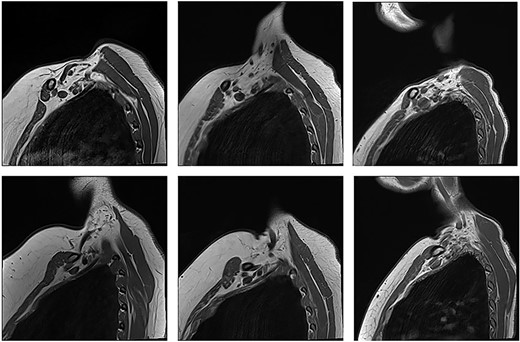

Patients with nTOS. The top rows are sequences with the arm in the neutral position. The bottom row is the corresponding patient with the arm raised.